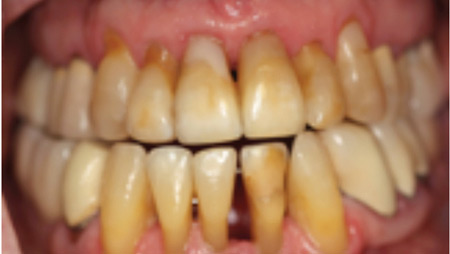

Dental Implants: A True Life Changing Experience for a Functionally Compromised Patient: A Case Report of a Maxillary and Mandibular Rehabilitation with a Dental Implant Retained Prosthesis

INTRODUCTION The goal of modern dentistry is to restore the patient to normal contour, function, comfort, esthetics, speech, and health, whether by removing caries from a tooth or replacing several teeth. What makes implant dentistry unique is the ability to achieve this goal, regardless of the atrophy, disease, or injury of the stomatognathic system. However, … Read more